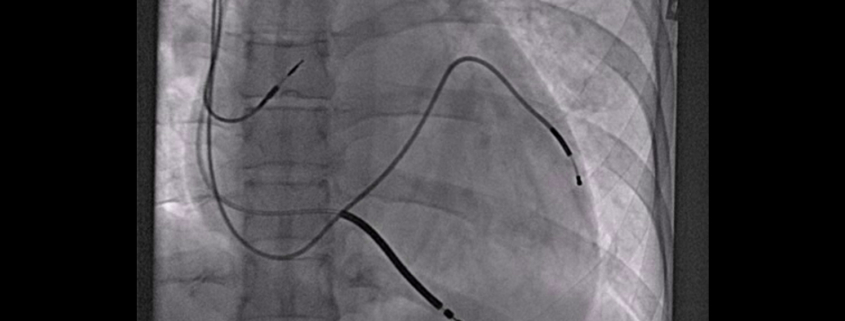

Privremeni elektrostimulator srca (ES) uključuje stimulaciju srca uslijed najčešće sporog srčanog rada (bradikardije) ili rjeđe brzog srčanog rada (tahikardije), kraće vrijeme dok se ne ukloni uzrok nastajanja poremećaja srčanog ritma ili do ugradnje trajnog elektrostimulatora.